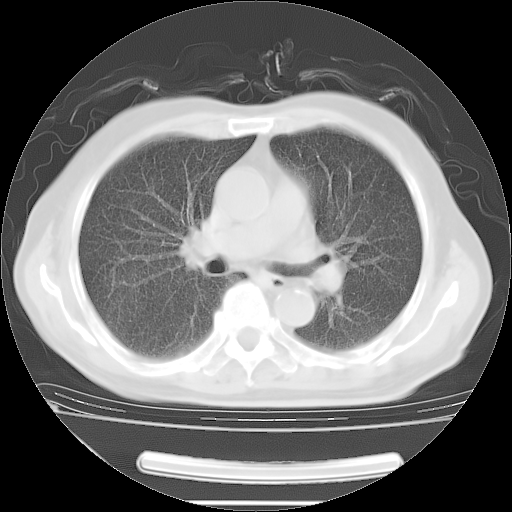

今天复查肺部CT,发现双肺广泛磨玻璃样改变。所以我把3月19日和5月9日相隔50天的肺部CT上传。请大家会诊。

5月9日肺部CT(在4月27日齐鲁医院肺部CT描述部分肺组织磨玻璃样改变,12天后肺组织广泛磨玻璃样改变)

大致读了系列胸部CT:纵隔窗无明显异常,肺窗:从4、27至今:主要是双肺中下野外带可见毛玻璃样改变,目前处于急性肺泡炎阶段,至于原因考虑1、结替组织或胶原血管性疾病所致?2、恶性疾病如恶组在肺部所致的表现或细支气管肺泡癌?3、药物或其它原因如肺蛋白沉着症所致肺泡炎目前不太可能?总之,明天就去请我院的呼吸科、感染科、血液科和临免专家会诊哈。